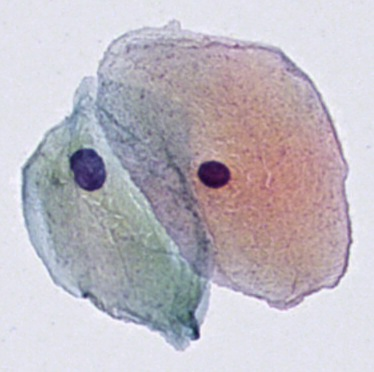

细胞实例分割数据集

数据集下载链接:http://ewz6s.avtk.cn/25

引入了新的大型细胞实例分割数据集 (CISD)。它包括3911个样品,其中包含至少两个接触或重叠的尿路上皮细胞。细胞实例由训练有素的细胞技术人员手动注释。所有样品均从 30 张数字细胞学载玻片中提取,这些载玻片用 9 种不同的 Papanicolaou 染色染色。细胞学载玻片使用豪洛捷 ThinPrep®5000 处理器从健康患者的尿液样本中制备,并常规使用安捷伦 Dako 盖染色仪®进行染色。最终使用具有21个焦平面的Hamamatsu NanoZoomer®S360对载玻片进行数字化,并以扫描仪自动对焦确定的最佳焦平面为中心。